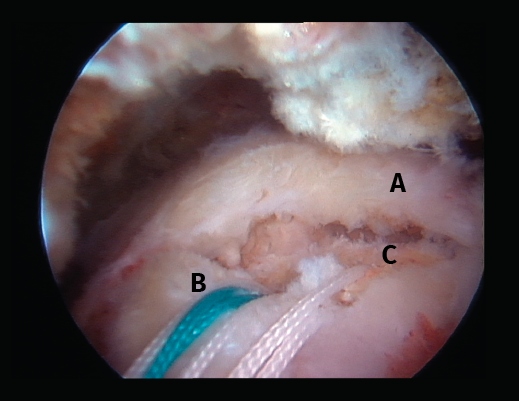

Figura 2. Rotura del manguito rotador en forma de U. A: tendón infraespinoso; B: tendón supraespinoso; C: cabeza humeral.

Figura 5. Rotura de tipo C1. A: rotura pequeña de espesor completo del supraespinoso; B: cabeza humeral.

Figura 6. Rotura de tipo C2. A: rotura del supraespinoso de escasa retracción; B: suturas que provienen de los anclajes; C: cabeza humeral.

Sin embargo, las clasificaciones basadas en el tamaño de la rotura deben ser bidimensionales, ya que la visión unidimensional puede ser engañosa, al mostrar el tamaño de la rotura solo desde el plano anteroposterior(4). Por esta razón, proponemos el sistema de clasificación del manguito posterosuperior sugerida por Snyder, que aporta información no solo del tamaño, sino del número de tendones afectados y la presencia de tejido cicatricial(7). En las lesiones de tipo C1 la lesión atraviesa todo el espesor del tendón y en el eje transversal es pequeña y punzante (Figura 5). Las de tipo C2 son roturas de espesor completo pero la distancia entre los extremos de la rotura es menor de 2 cm con escasa retracción (Figura 6). En las de tipo C3 la rotura afecta en sentido transversal entre 3 y 4 cm con mayor retracción implicando 2 tendones (Figura 7). Y las de tipo C4 son la rotura masiva del manguito de los rotadores con una afectación de espesor completo de toda la anchura de 2 o más tendones asociando importante retracción (Figura 8).